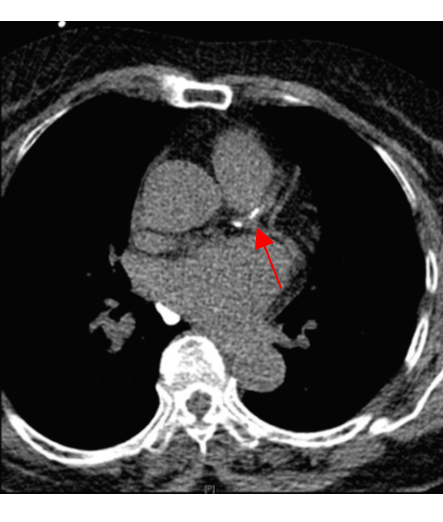

- CT 스캔: 관상동맥 석회화의 상태를 명확하게 볼 수 있는 비침습적인 검사 방법으로, 좌우 심장관의 석회화 수준을 확인할 수 있습니다. 많은 경우, 이 검사는 영화 한 편 보는 시간 안에 가능하여 매우 효율적입니다.